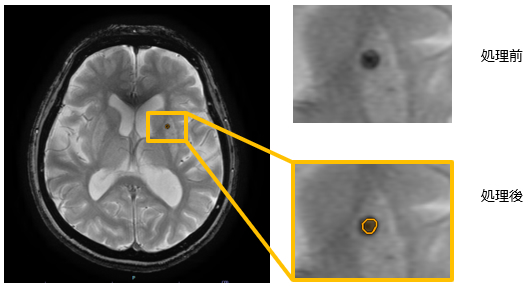

「頭部T2*低信号強調フィルタ」は、T2*強調画像から周辺組織と比較して低信号の領域を抽出します。

一般的に、頭部T2*強調画像で低信号となる領域は出血であることが多く、本機能により微小出血の診断支援に繋がることが期待されます。今回拡充する「脳区域ラベリング(MR)」機能の解剖情報を反映した所見文候補作成支援機能と併用することで、読影ワークフロー全体を支援します。

T2*強調画像で「頭部T2*低信号強調フィルタ」を用いた表示

所見文候補作成支援機能により、関心領域の場所や大きさなどの計測値情報を自動入力